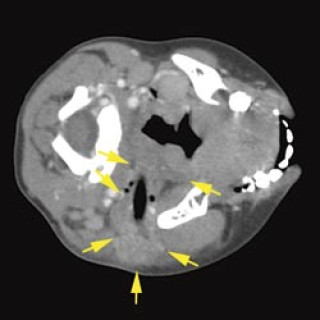

En 23 år gammel førstegangsgravid kvinne som fra tidligere stort sett var frisk, ble innlagt i lokalsykehus ved svangerskapslengde 22 uker + 2 dager, med en seks dagers sykehistorie med generell sykdomsfølelse, feber opptil 40 °C, kvalme, oppkast og anoreksi. I tillegg hadde hun fått økende ansiktsødemer, korsryggssmerter, hodepine og synsforstyrrelser. Svangerskapet hadde vært ukomplisert frem til det aktuelle. Hun var normotensiv. Blodprøvene viste kreatinin 236 µmol/l, karbamid 13 mmol/l, urat 410 µmol/l, leukocytter 15,0 · 10⁹/l, CRP 106 mg/l og trombocytter 86 · 10⁹/l. Leverprøvene var...